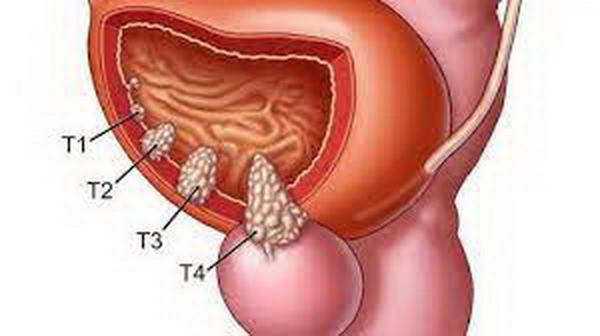

Dấu hiệu ung thư tiền liệt tuyến

Giai đoạn đầu của ung thư tiền liệt tuyến thường không có triệu chứng rõ ràng. Ở giai đoạn sau, một số dấu hiệu có thể xuất hiện như:

- Tiểu tiện khó khăn: Buồn tiểu nhưng không thể đi, dừng giữa chừng, hoặc tiểu nhiều hơn bình thường.

- Đau khi đi tiểu: Khối u chèn ép niệu đạo gây cảm giác đau.

- Xuất hiện máu trong nước tiểu: Có thể chỉ là vệt hồng; cần đi khám ngay nếu thấy.

- Khó duy trì sự cương cứng: Khối u cản trở lưu lượng máu đến dương vật.

- Máu trong tinh dịch: Thường không được chú ý, chỉ làm tinh dịch hơi hồng.

- Đau ở lưng, hông, đùi: Đây là dấu hiệu phổ biến của bệnh.

- Tiểu đêm: Đi tiểu nhiều hơn hai lần mỗi đêm có thể là dấu hiệu cảnh báo.

- Tiểu rắt: Rò rỉ nước tiểu không tự chủ cần được lưu ý.

Ung thư tiền liệt tuyến có thể được phát hiện qua xét nghiệm PSA. Khi di căn, bệnh có thể gây ra đau xương và ảnh hưởng đến tủy sống, dẫn đến yếu chân hoặc không kiểm soát đại tiểu tiện. Những triệu chứng thường phát triển âm thầm, làm khó khăn trong việc phát hiện sớm. Phẫu thuật cắt bỏ tuyến tiền liệt bằng laser